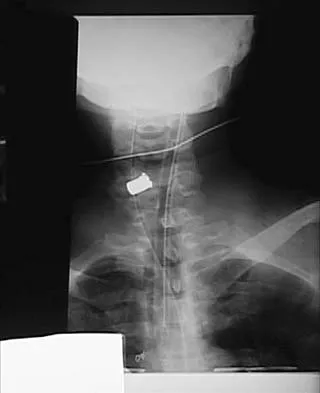

A 28-year-old professional dancer reports a 3-month history of progressive pain in the posterior aspect of the left ankle. Her symptoms are worse when she assumes the en pointe position. Examination reveals tenderness to palpation at the posterolateral aspect of the ankle posterior to the peroneal tendons which is made worse with passive plantar flexion. There is no nodularity, fluctuance, or tenderness of the Achilles tendon. The neurovascular examination is unremarkable. A lateral radiograph and MRI scan are shown in Figures 16a and 16b, respectively. Management should consist of

The imaging studies reveal findings typical of the os trigonum syndrome. This condition results from inflammation between the os trigonum and the adjacent talus. The symptoms of posterior ankle pain are exacerbated by plantar flexion, which stresses the fibrous union between these two bones. Definitive management of the high-level athlete involves excision of the os trigonum from a medial approach, although arthroscopic excision has also been described. The os trigonum is not an intra-articular structure; therefore, ankle arthroscopy is neither diagnostic nor therapeutic. Abramowitz Y, Wollstein R, Barzilay Y, et al: Outcome of resection of a symptomatic os trigonum. J Bone Joint Surg Am 2003;85:1051-1057. Mouhsine E, Crevoisier X, Leyvraz P, et al: Post-traumatic overload or acute syndrome of the os trigonum: A possible cause of posterior ankle impingement. Knee Surg Sports Traumatol Arthrosc 2004;12:250-253.